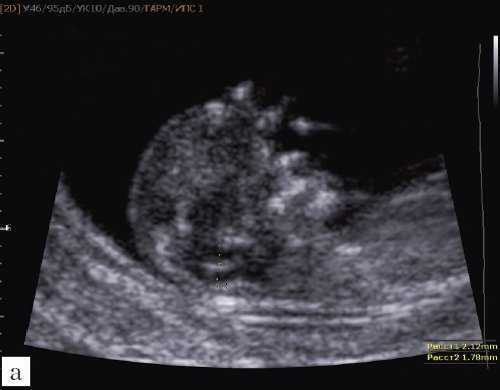

Рис. 4. Измерение и взаимоотношение ножек "осьминожки" - ствола мозга и IV желудочка у плода, беременность 12 недель.

Измерение ножек "осьминожки".

Красный цвет - диэнцефалон (таламус), со стволом мозга (верхняя ножка) и IV желудочком (нижняя ножка); желтый цвет - большая цистерна головного мозга; синий цвет - воротниковое пространство.